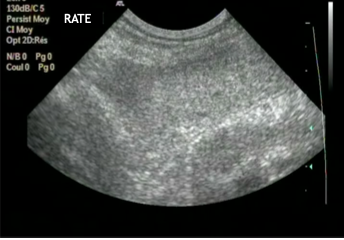

Que remarquez-vous d’anormal?

rein hyperéchogène par rapport au foie : anormal !

ici : intoxication éthylène glycol